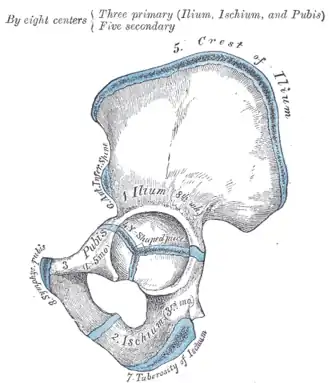

Тазовая кость (лат. os coxae) — это обозначение для парной кости правой и левой, которые относятся к поясу нижних конечностей, а вместе с крестцом и копчиком образуют таз. Используется также название безымянные кости. Каждая из тазовых костей в свою очередь образована тремя составляющими: подвздошной костью, седалищной костью и лобковой костью, которые соединяются посредством хряща в области вертлужной впадины, служащей местом соединения тазовой кости с бедренной. В возрасте 14-16 лет эти три кости срастаются, образуя единую тазовую кость.

Подвздошная кость (лат. os ilium) составляет ближайшую к позвоночнику часть пояса задних конечностей или таза, сочленяющуюся с крестцовыми позвонками. Она ясно выражена уже у амфибий. У человека она сочленяется крестцовой костью, являющейся результатом слияния 5 позвонков, и в области вертлужной впадины, служащей для помещения головки бедра, срастается с двумя другими тазовыми костями: седалищной и лобковой. Верхний край подвздошной кости человека закруглён, передний и задний образуют по два выступа (лат. spinae anterior superior, ant. inferior, posterior superior, post. inferior), а на своей внутренней и наружной поверхности она имеет изогнутое линейное возвышение (linea arcuata inferior et exterior).

Седалищная кость (лат. os ischii) — одна из костей пояса задних или нижних конечностей, иначе таза. Она ясно выражена уже у амфибий. У человека она состоит из следующих частей: тело, которое соединяется сверху с подвздошной костью, а спереди с лобковой горизонтальной ветвью и вместе с этими костями образует тазовую кость (os coxae). В месте соединения этих костей находится вертлужная впадина (acetabulum) для приёма бедренной головки. От тела вниз на задней части отходит нисходящая ветвь (ramus descendens), образующая на нижнезаднем углу седалищный бугор (Tuberculum ossis ischii) и продолжающаяся вперёд и вверх в виде восходящей ветви (ramus ascendens). Последняя с нисходящей ветвью лобковой кости, и таким образом между телом седалищной кости, её обеими ветвями и обеими ветвями лобковой образуется овальной формы отверстие (foramen obturatum sivo ovale).

Лобковая кость (лат. os pubis) — одна из трёх костей, образующих при сращении тазовую кость. Состоит из тела и двух ветвей. Ветви и тело лобковой кости образуют запирательное отверстие (foramen obturatoris), закрытое запирательной мембраной. Две лобковые кости, срастаясь, образуют переднюю стенку таза.

Тазовые кости новорождённого (слева) и ребёнка 12-13 лет, синим отмечена хрящевая ткань -